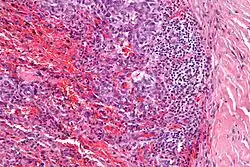

| Micrograph showing an angiomatoid fibrous histiocytoma. H&E stain. |

It is characterized by cystic blood-filled spaces and composed of histiocyte-like cells. A lymphocytic cuff is common. It often simulates a vascular lesion, and was initially described as doing this.[1]